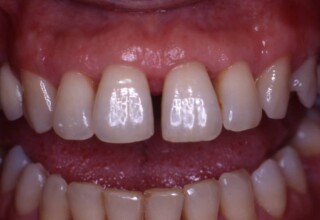

Αποκατάσταση διαστημάτων μεταξύ κεντρικών και πλαγίων τομέων

Τα διαστήματα έχουν δημιουργηθεί κυρίως λόγω των στενών πλαγίων. Μετά την ολοκλήρωση της ορθοδοντικής θεραπείας τα διαστήματα “έκλεισαν” με την τοποθέτηση δύο αποκαταστάσεων σύνθετης ρητίνης.